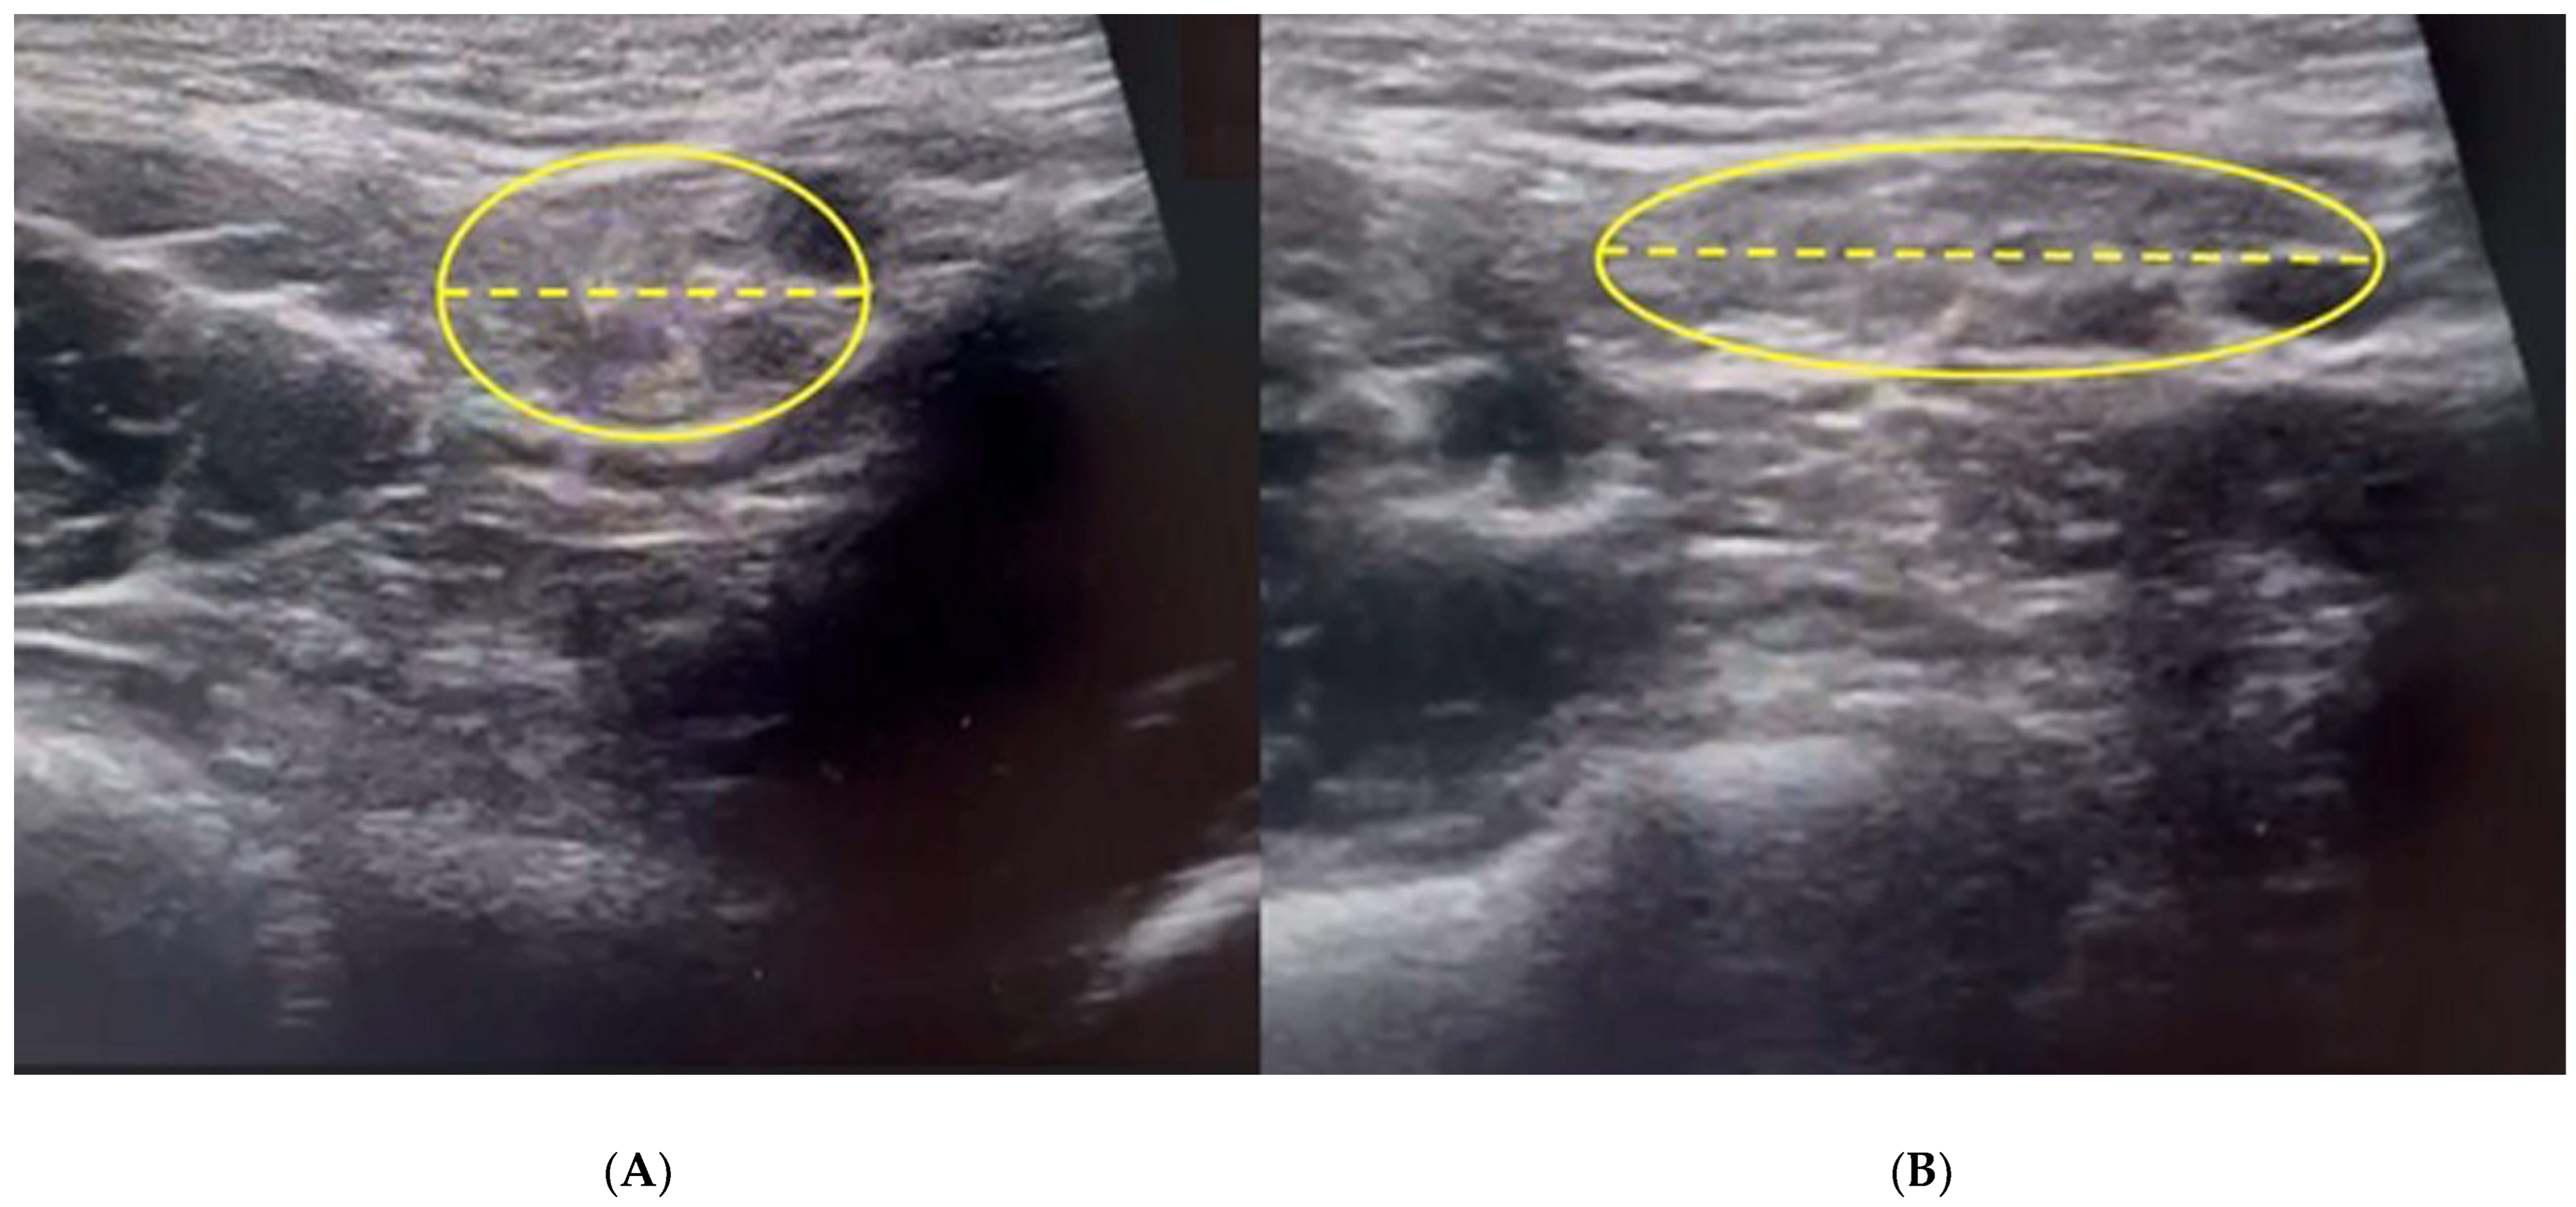

3.2. Dynamic Ultrasonography Examination